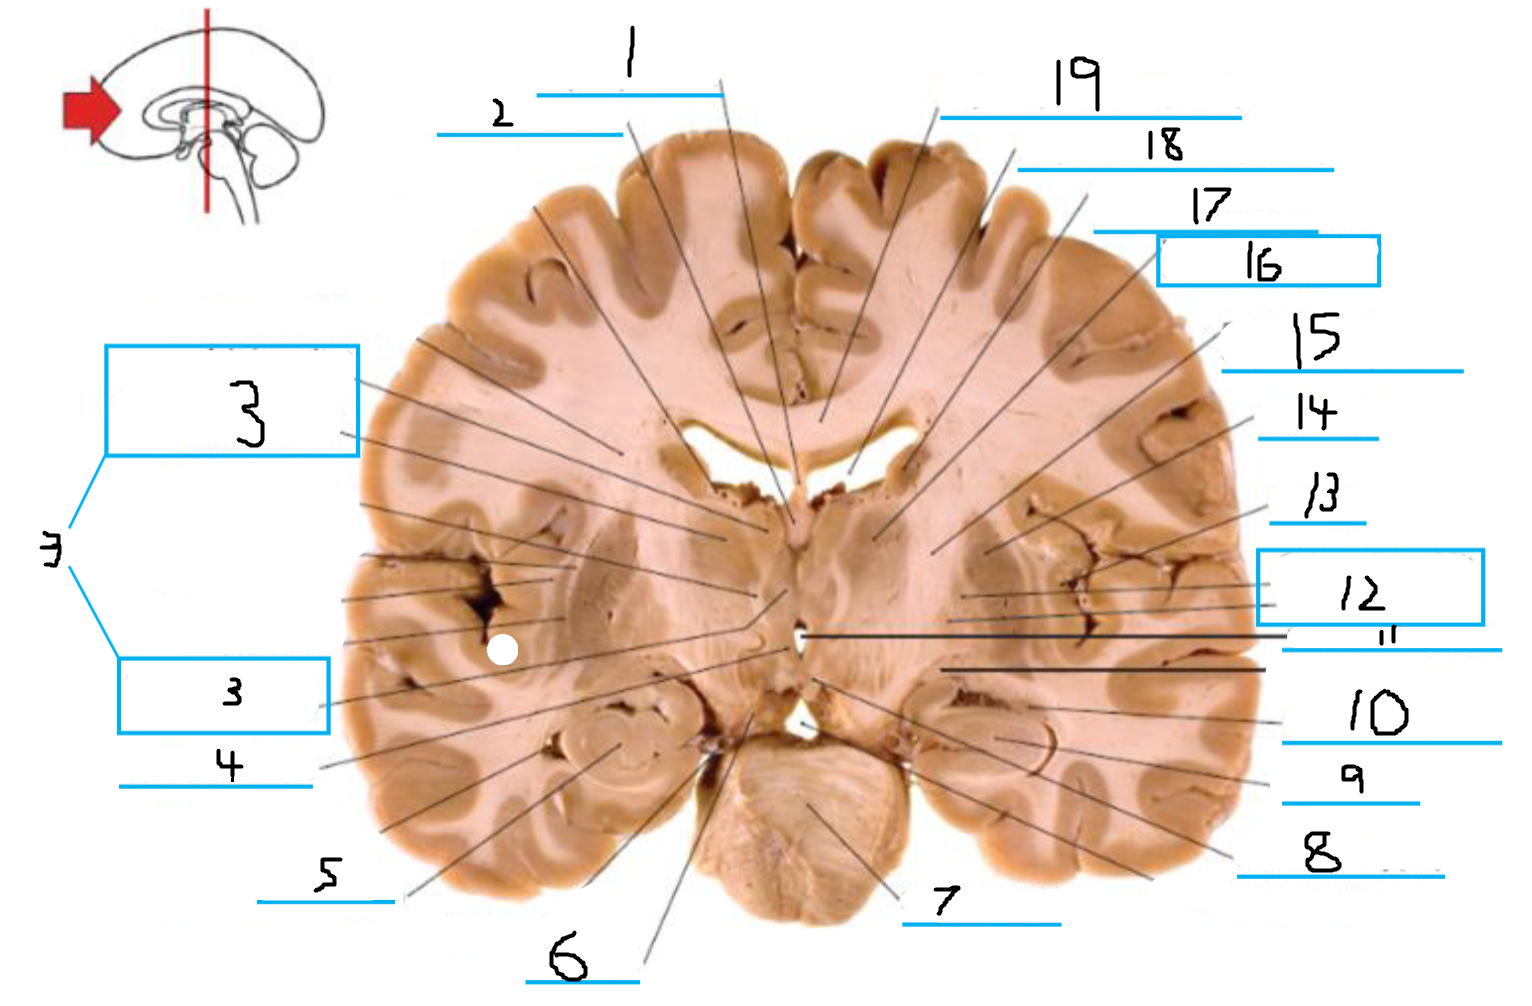

#1 is the:

Cingulate Gyrus

#2 is the:

Septum Pellucidum

#3 is the:

Lateral Ventricle

#4, #7, and #12 is the:

Fornix

#5 is the:

Third Ventricle

#6 is the:

Anterior Commissure

#8 and #11 is the:

Amygdala

#9 is the:

Hypothalamus

#10 is the:

Mammillary Body

#13 is the:

Insula

#14 is the:

Globus Pallidus

#15 is the:

Putamen

#16 is the:

Internal Capsule

#17 is the:

Caudate

#18 is the:

Corpus Callosum

#3 and #16 are the:

Thalamus

#4 is the:

#5 and #9 is the:

Hippocampus

Crus Cerebri

#7 is the:

Basilar Pons

#8 is the: